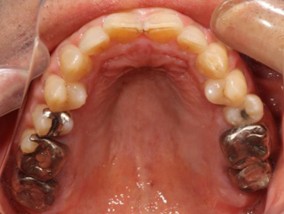

70代 女性

治療前

- 70代/女性

- 患者の具体的な症状

- 下顎の奥歯が義歯で噛みづらいため、インプラント治療を希望

- 検査方法

- コーンビームCT、レントゲン撮影

- 診断結果

- 左下6欠損

- 治療詳細

- 左下6インプラント埋入1本、骨造成なし、局所麻酔

- 通院回数

- 8回

- 治療期間

- 6か月